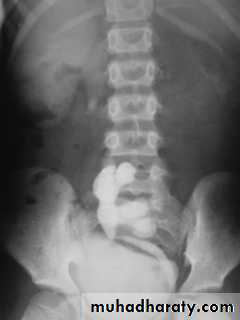

21- Horse shoe kidney